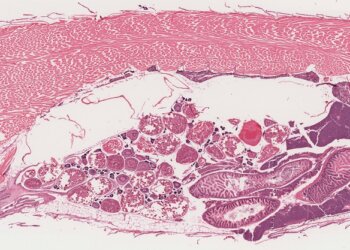

A importância do uso de biomarcadores histológicos em estudos de contaminação ambiental Thayzi Zeni (30/06/2014) A histologia é uma ferramenta...

Read moreDetailsBiomarcadores de contaminação ambiental: um enfoque na avaliação histológica para o diagnóstico...